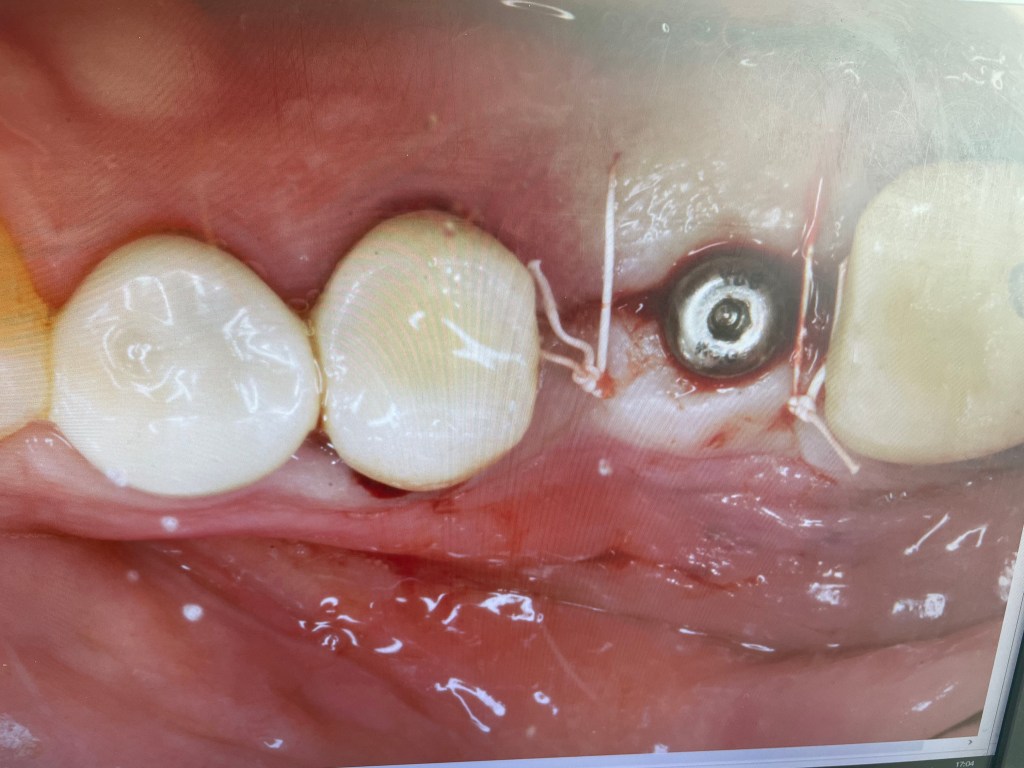

Only days after the extraction of two molars I return to the chair. This time it is an operation to screw in another implant. It is not much fun but better than being outside.